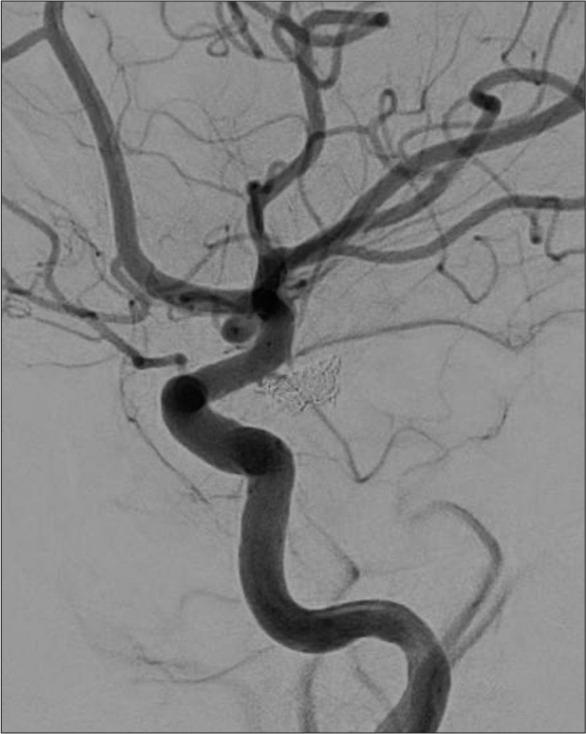

CASE DESCRIPTION

The case describes a 49-year-old Filipino woman with a history of hypertension who presented with symptoms strongly suggesting KBS following subarachnoid hemorrhage, including behaviors such as hyperorality, hypermobility, placidity, hypermetamorphosis, and hypersexuality along with memory disturbance. She was managed as a case of brief psychotic disorder initially with olanzapine, then on the second presentation as a case of delirium with risperidone.

该病例描述了一名49岁有高血压病史的菲律宾女性,蛛网膜下腔出血后出现强烈提示KBS的症状,包括口欲亢进、多动、平静、变换症和性欲亢进等行为以及记忆障碍。她最初被当作短暂性精神病性障碍病例用奥氮平治疗,第二次就诊时被当作谵妄病例用利培酮治疗。